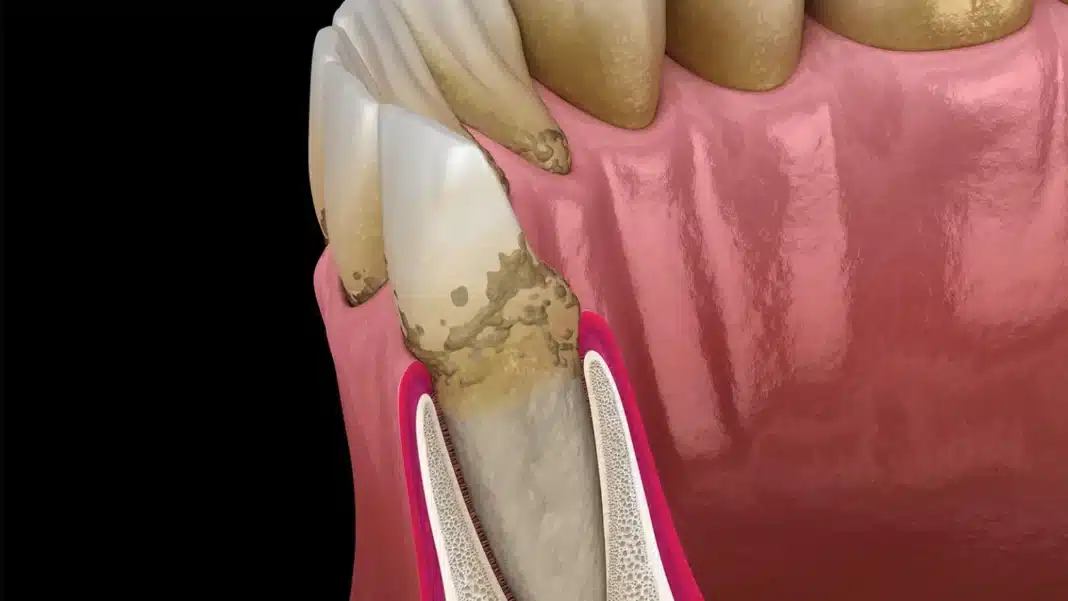

Παλαιότερες μελέτες παρατήρησης έχουν επιβεβαιώσει τη συσχέτιση μεταξύ ασθενών με ρευματοειδή αρθρίτιδα ΡΑ και υψηλότερων επιπέδων περιοδοντικής νόσου (νόσου των ούλων). Τα αντισώματα κατά των πρωτεϊνών κιτρουλλινικής προέλευσης (ACPA) βρίσκονται στο αίμα των περισσότερων ασθενών με ρευματοειδή αρθρίτιδα ΡΑ.

Η συσχέτισή τους είναι τόσο στενή ώστε τα αντισώματα κατά των πρωτεϊνών κιτρουλλινικής προέλευσης ACPA που ανιχνεύονται στο αίμα αποτελούν το καλύτερο εργαλείο έγκαιρης ανίχνευσης για μελλοντική παθολογία της ρευματοειδούς αρθρίτιδας ΡΑ, καθώς μπορούν να προηγηθούν της κλινικής διάγνωσης κατά αρκετά έτη. Η νόσος των ούλων είναι συγκεκριμένα πιο συχνή σε άτομα με ρευματοειδή αρθρίτιδα ΡΑ που έχουν επίσης αντισώματα κατά των πρωτεϊνών κιτρουλλινικής προέλευσης ACPAs στο αίμα τους.

Σε μια μελέτη με επικεφαλής το Πανεπιστήμιο του Στάνφορντ, οι ερευνητές θέλησαν να διερευνήσουν αν αυτές οι επικαλυπτόμενες παρατηρήσεις θα μπορούσαν να συνδεθούν καλύτερα. Οι ερευνητές ανέλυσαν βακτηριακό RNA σε δείγματα αίματος που συλλέχθηκαν από ομάδα 5 ασθενών με ρευματοειδή αρθρίτιδα ΡΑ με και χωρίς νόσο των ούλων σε εβδομαδιαίες χρονικές στιγμές επί ένα έτος. Εντόπισαν υπογραφές RNA μέσα σε ομάδες ενεργοποιημένων ανοσοκυττάρων που συσχετίζονταν τόσο με την παρουσία στοματικών βακτηρίων στο αίμα όσο και με τις εξάρσεις της αρθρίτιδας σε ασθενείς τόσο με ρευματοειδή αρθρίτιδα ΡΑ όσο και με περιοδοντική νόσο. Διαπιστώθηκε ότι τα βακτήρια ήταν κιτρουλλιωμένα (τροποποιημένα ενζυμικά) και αυτή η μεταβολή παρείχε τους στόχους για την επίθεση των αντισωμάτων κατά των κιτρουλλιωμένων πρωτεϊνών, καθώς και την αύξηση του αριθμού των αντισωμάτων που ανταποκρίνονταν.

Οι ερευνητές διαπίστωσαν περαιτέρω ότι τα βακτήρια ήταν ήδη κιτρουλλινωμένα σε δείγματα από το στόμα. Αν και αυτή ήταν μια ελπιδοφόρα παρατήρηση, εξακολουθούσε να είναι μια συσχέτιση στη μέση των προηγουμένως γνωστών επικαλυπτόμενων συνθηκών.